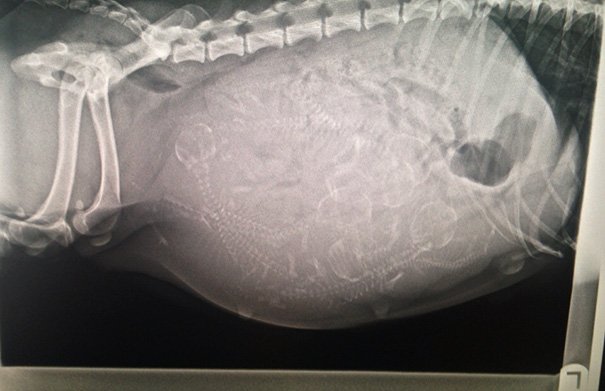

Итак, как выглядят рентгеновские снимки беременных животных:

ещё одна морская свинка